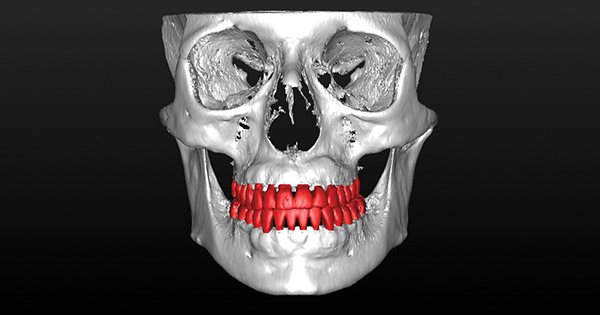

Fig 7. Preoperative CBCT 3D tooth position and regional bone anatomy. Note maxillary hypoplasia, malocclusion, and dentoalveolar deficiencies.

Figure 7